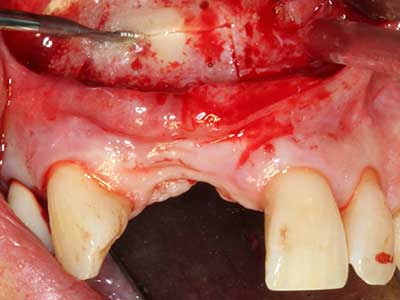

Пиезохирургията има допълнителни предимства при събиране на костни блокове. В допълнение към високата прецизност при остеотомията, описана по-горе, употребата на фините режещи накрайници значително намаляват загубата на материал. Голяма загуба на материал по време на събиране може да се очаква с дебелите накрайници, особено при употреба на борери Линдеман (Lakshmiganthan, Gokulanathan et al. 2012). Базалното разделяне, което е необходимо, особено за присадка на блок при ретромолар, е улеснено от специално създадени правоъгълни триони. В резултат на това, пиезохирургията е разглеждана като прецизна, улеснена и безопасна процедура за събиране на костни блокове в ретромоларното пространство (Happe 2007) (Фиг. 1-12).